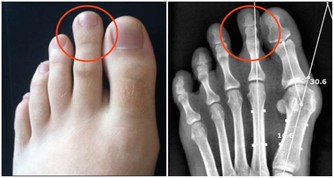

03.緩解關節炎,薑黃中的薑黃素屬於多酚類物質,具有抗發炎、抗氧化等作用。能有效消除關節炎症,抑制關節炎病發。